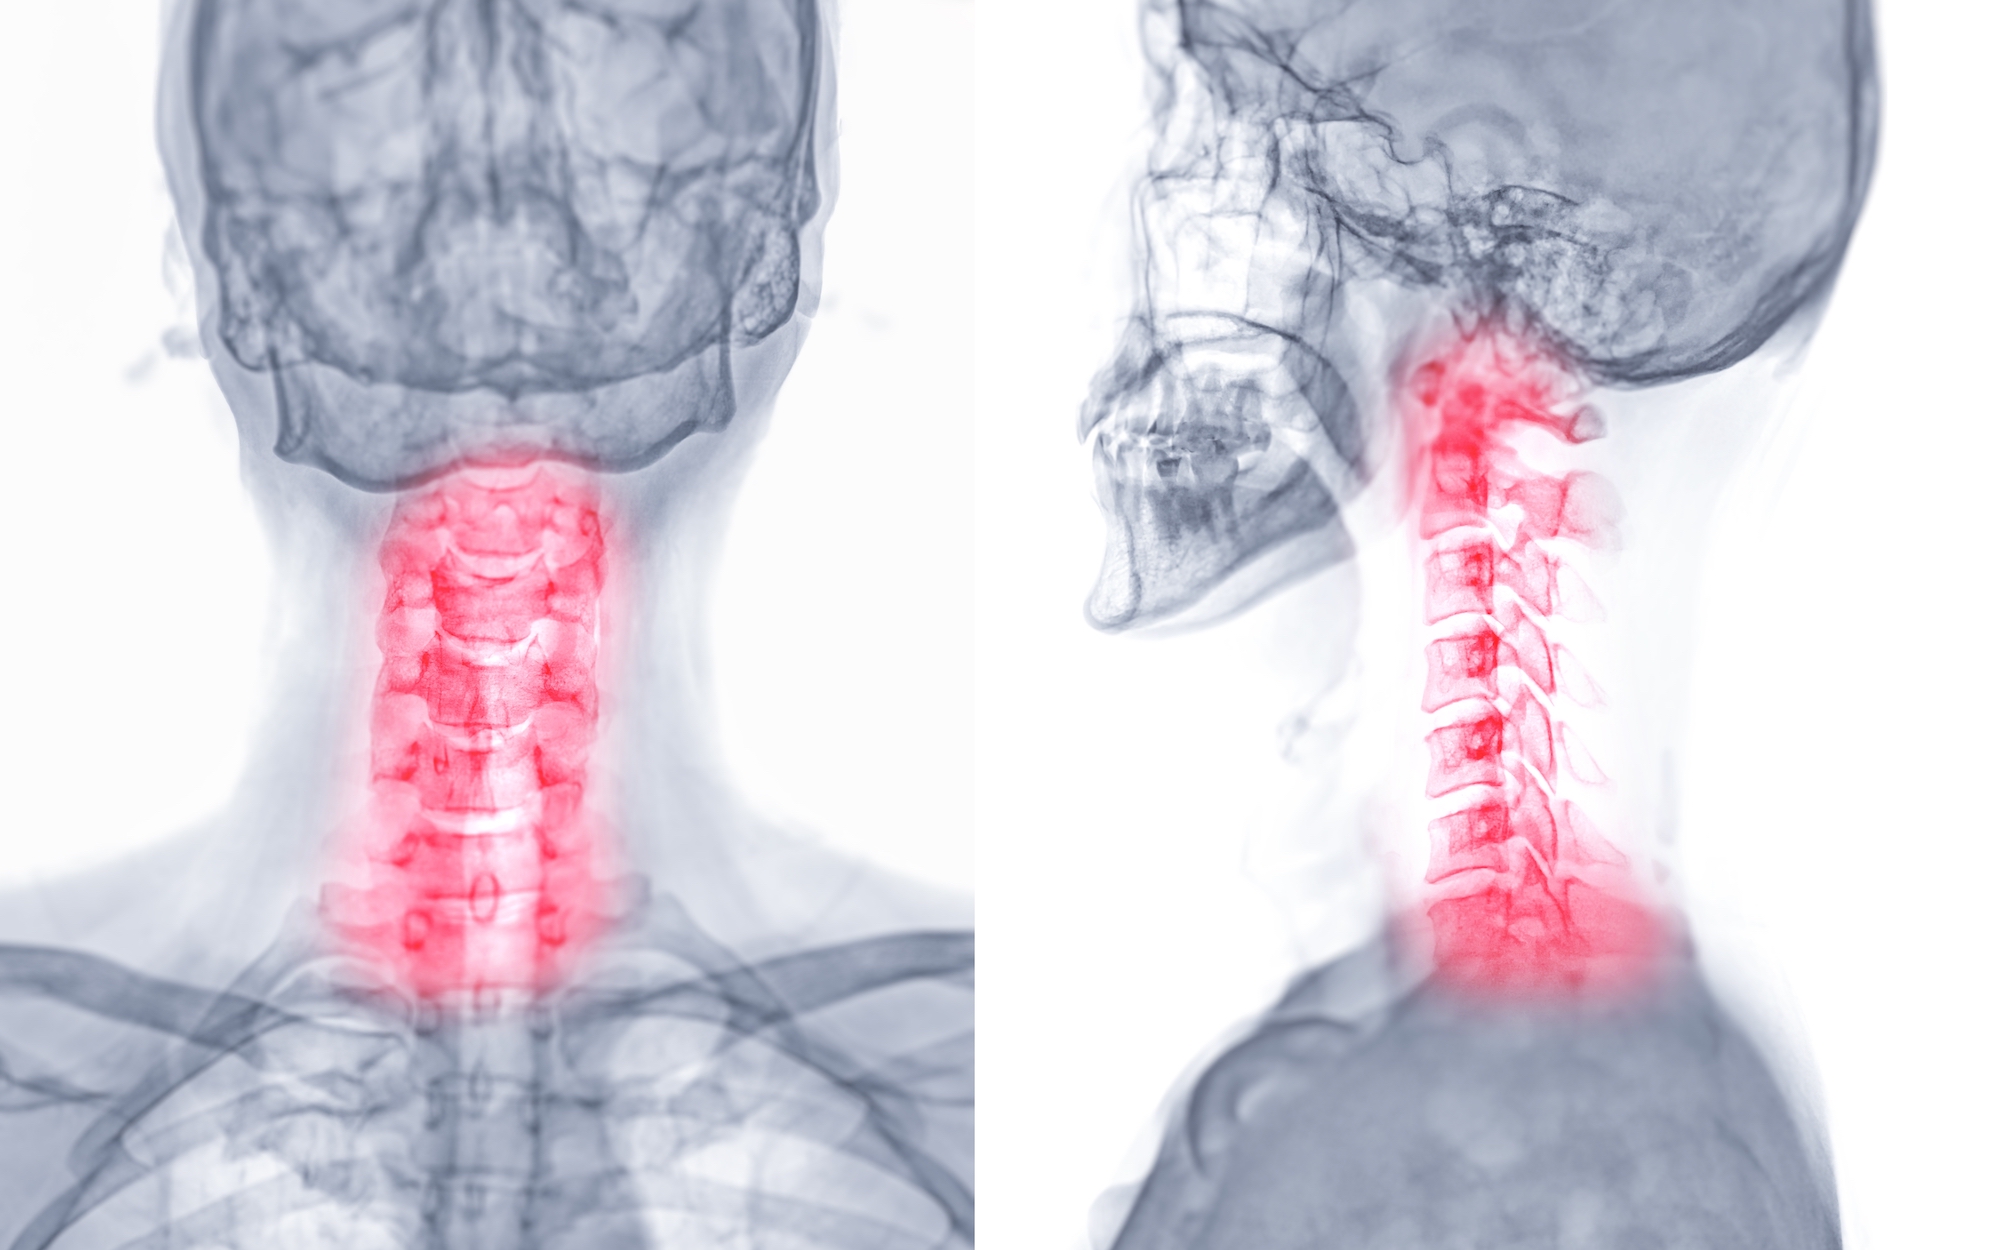

Αυχενική δισκοκήλη (κήλη μεσοσπονδύλιου δίσκου)

Η κήλη στον αυχένα ή αυχενική δισκοκήλη είναι μια πάθηση της σπονδυλικής στήλης που συμβαίνει στον αυχένα, την περιοχή δηλαδή της σπονδυλικής στήλης που εκτείνεται από το κρανίο έως το πάνω μέρος της πλάτης Η αυχενική δισκοκήλη ή πρόπτωση δίσκου προκύπτει όταν οι μεσοσπονδύλιοι δίσκοι, τα "μαξιλαράκια" τα οποία βρίσκονται μεταξύ των σπονδύλων και λειτουργούν ως αντικραδασμικά, τραυματίζονται ή εκφυλίζονται.

Αυτό μπορεί να οδηγήσει σε πρόβλημα, καθώς ο δίσκος μπορεί να εκτοπιστεί και να πιέσει τα νεύρα ή τον νωτιαίο μυελό, προκαλώντας πόνο, μούδιασμα αδυναμία στα άνω και στα κάτω άκρα.

Στη αυχενική δισκοκήλη ένα κομμάτι του πυρήνα του δίσκου προβάλλει προς τα έξω μέσα από μια ρωγμή του ινώδους δακτυλίου και πιέζει την εξερχόμενη νευρική ρίζα

Για τη διάγνωση της αυχενικής δισκοκήλης είναι απαραίτητη η λεπτομερής λήψη του ιατρικού ιστορικού του ασθενή από τον χειρουργό, η καταγραφή όλων των συμπτωμάτων που έχει παρατηρήσει, ώστε να διαπιστωθεί αν συνδέονται με τη συγκεκριμένη πάθηση, καθώς και η κλινική και νευρολογική εξέτασή του. Οι απλές ακτινογραφίες συμβάλλουν και αυτές σε μεγάλο βαθμό στη διαδικασία της διάγνωσης μιας δισκοκήλης αυχένα, αλλά η μαγνητική τομογραφία είναι η καλύτερη εξέταση, καθώς είναι αυτή μέσω της οποία θα διαγνωστεί με σιγουριά η πάθηση.